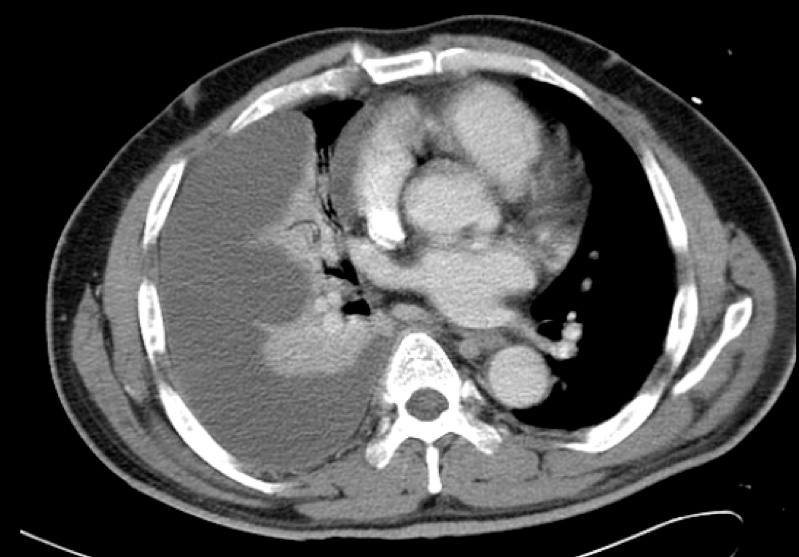

The chest X-ray and subsequent representative CT thorax images are given below, showing a massive right-sided pleural effusion that is also multi-loculated..